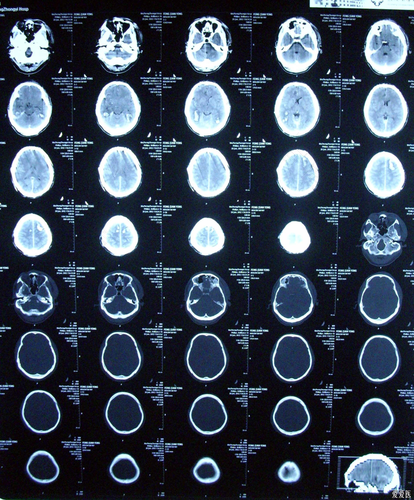

闭合性颅脑损伤是由于外力的重大撞击导致的。大多数的人患有这种疾病的原因都是由于车祸、跌倒,还有一些是由于产伤导致的。很多的疾病都会留下后遗症,下面就说说闭合性颅脑损伤后遗症。

闭合性颅脑损伤,也分为轻型、中型、重型的。一般轻型的脑损伤结合着一般的治疗,卧床一周后就会明显的得到改善,在恢复期间只需要注意观察患者的表现就可以了。大多数的患者通过调养后就会恢复到正常的状态中。对于一些中型的脑损伤就需要通过一些治疗来改变患者的病情,大多数的患者都需要住院接受治疗的。

如果患者是严重脑损伤,就需要接受手术的治疗,防止颅内的压力增高,以防止脑瘫的形成,还要在手术后,保证营养的供给,加强平时的锻炼,防止脑瘫或者一些其他严重的现象发生。